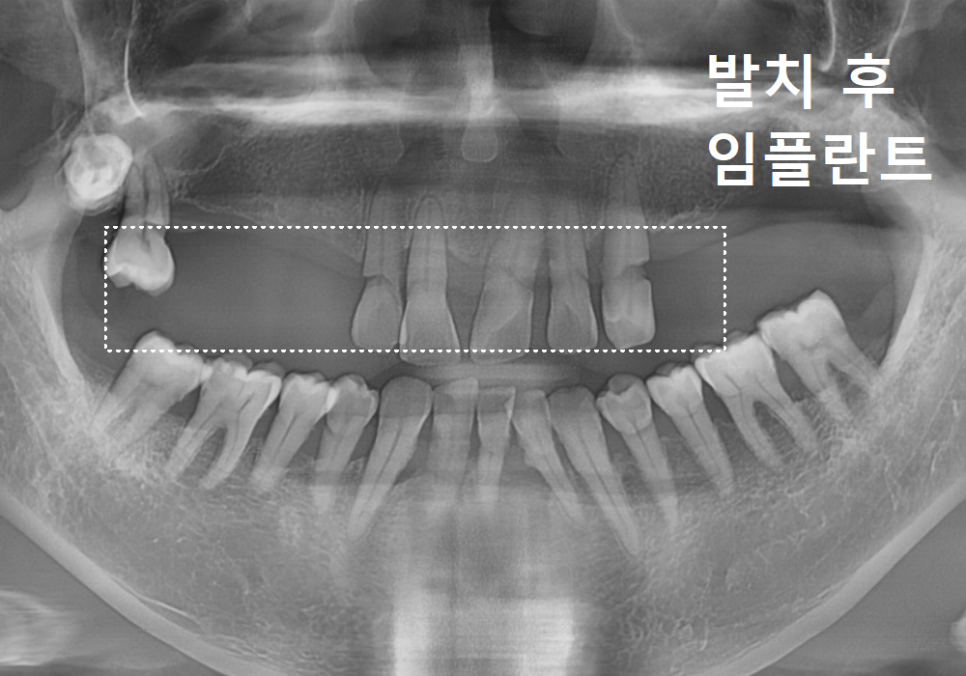

사진 오른쪽 끝을 보시면 #18번 사랑니가

하나 매복되어 있는 게 보이실 거예요.

이 사랑니는 이미 뼈 안쪽

깊숙이 자리 잡고 있어서,

환자분께 가장 무리가 가지 않는 방향으로

매복된 상태로 두기로 했습니다.

이번 케이스는 사랑니를 제외한 치아를 모두

발치하고 총 7대의 임플란트를 심기로 했습니다.

보통 빠진 치아 수대로

임플란트를 심기도 하지만,

환자분의 상태에 따라 '브릿지 보철'을 이용해

식립 개수를 조절할 수 있거든요~